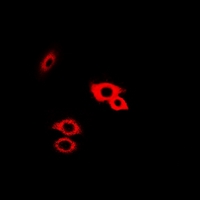

Immunofluorescence analysis of HeLa cells using Galactosidase alpha ) antibody . Blue: DAPI for nuclear staining.